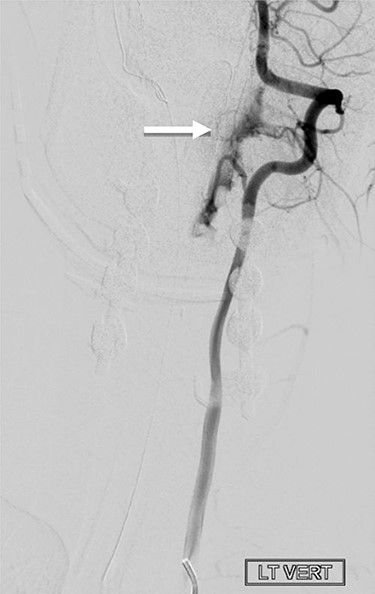

Whole spine MRI showed a C3–C6 left extradural lesion causing marked compression on the spinal cord (Fig. 1). Cerebral angiography confirmed an arteriovenous fistula (Fig. 2).

Cerebral angiography, with left vertebral artery injection, demonstrates evidence of arteriovenous shunting. The lesion is suggestive of arteriovenous fistula in the left upper cervical region. The arterial supply, from a hypertrophied branch of the left vertebral artery, was arising at the level of C2. However, the fistulous connection was at the level of C3 and C4.

The patient was kept on a cervical collar and was started on physiotherapy program. Her neurological symptoms were maintained at baseline. There was a large venous pouch, as suspected intraoperatively, along the left side of the spinal canal draining into the upper cervical venous plexus (Fig. 2). Embolization of the fistulous connection was performed after selective catheterization of the branch of the left vertebral artery. After embolization, there was no evidence of residual arteriovenous shunting.